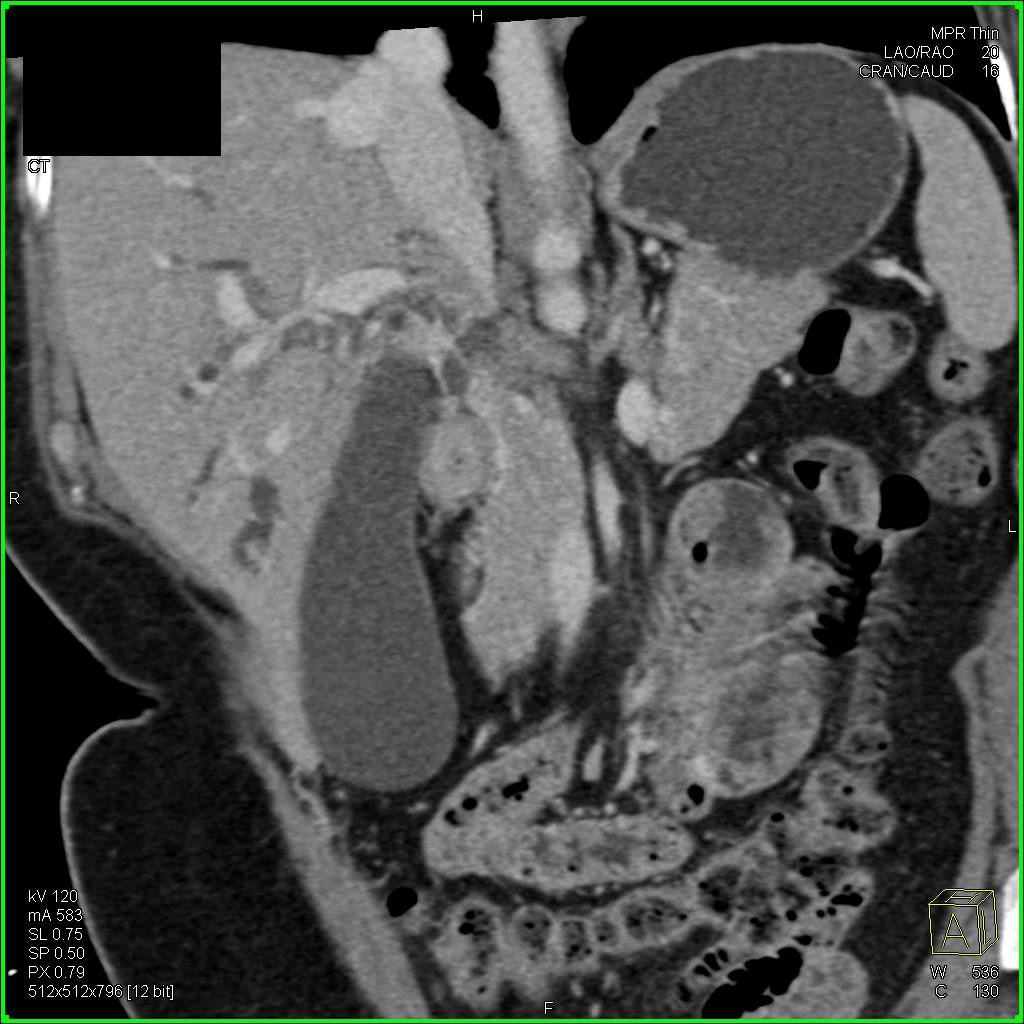

Hepatocellular Carcinoma (Hepatoma) with Neovascularity